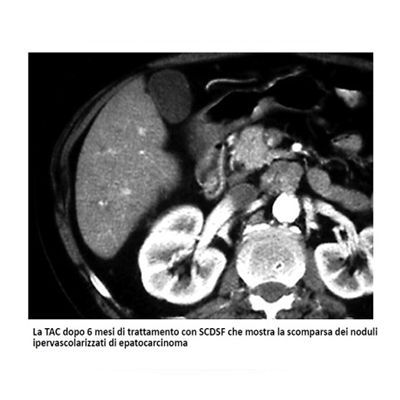

- Valutazione, terapie integrate e di supporto alle malattie tumorali del fegato (epatocarcinoma)